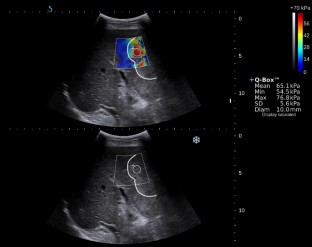

A total of 175 FLLs in 169 patients were prospectively analyzed. The study population was divided into a training cohort (n = 122) and a validation cohort (n = 53). The maxima, minima, mean, and standard deviation of 2D-SWE measurements were expressed in kilopascals (Emax, Emin, Emean, and ESD). The ultrasonics technique was used to extract the features from the 2D-SWE images. Support vector machine was used to establish two prediction models: the ultrasomics score (ultrasomics features only) and the combined score (SWE measurements and ultrasomics features). The diagnostic performance of the models in differentiating FLLs was analyzed.

Fig. 1